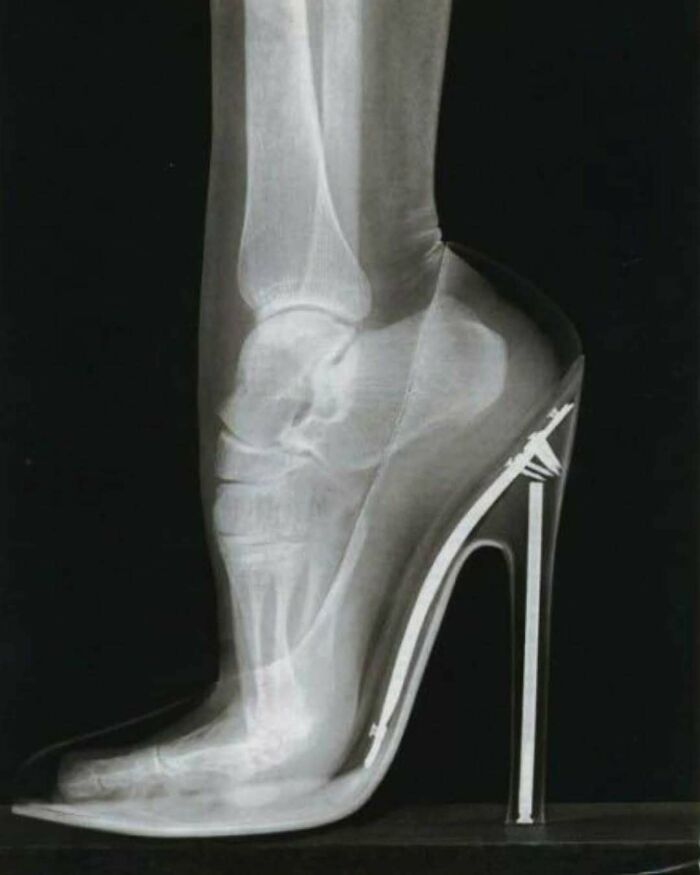

#2 Premýšľali ste niekedy nad tým, ako vyzerá noha pod röntgenom pri nosení vysokých podpätkov?